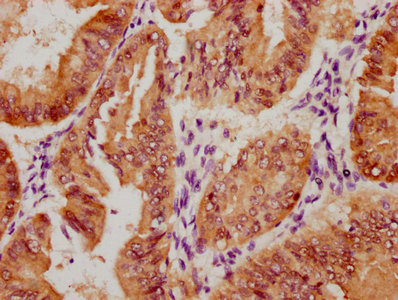

Immunohistochemistry of paraffin-embedded human liver tissue using CSB-PA001572EA01HU at dilution of 1:100